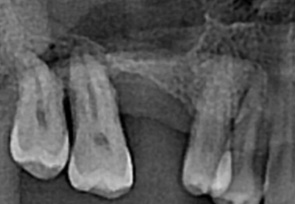

before

-

after